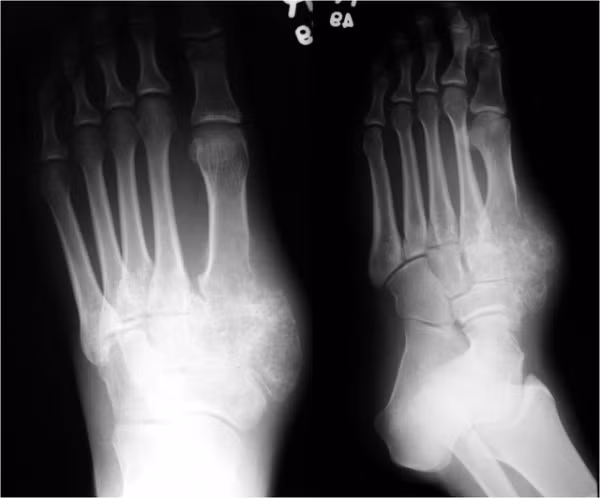

Ung thư chân. Rất hiếm người bị ung thư này vì nó không phổ biến, nhưng đừng bao giờ bỏ qua. Mọi người nên để ý đến những dấu hiệu bất thường ở chân như một nốt ruồi đang lớn dần, cảm giác lạ, đau ở chân. Đó có thể là dấu hiệu của ung thư da, mạch máu, xương hoặc dây thần kinh.

Trong đó, ung thư da là phổ biến nhất trên chân. Tuy nhiên, nó vẫn được xếp vào dạng hiếm khi chỉ có khoảng 10 ca mắc ở Mỹ mỗi năm. Ung thư da ở chân thường là dạng u hắc tố. Tỷ lệ những khối u này xuất hiện ở chân là 3 đến 5%. Nó liên quan nhiều hơn đến yếu tố di truyền hoặc hóa chất gây ung thư chứ không phải ánh sáng mặt trời.